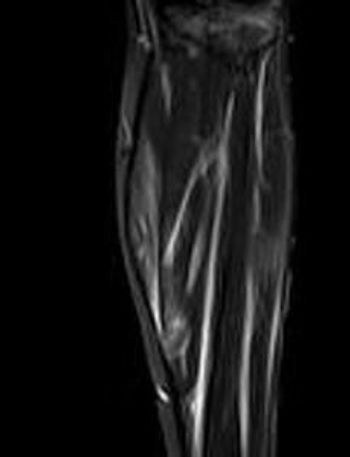

She presented with such severe calf pain she could no longer walk unassisted, with a months-long history of fever of unknown origin. What does the MRI show?

This young woman presented with severe leg pain, night sweats, and fever of unknown origin. The diagnosis of polyarteritis nodosa had several unusual features.